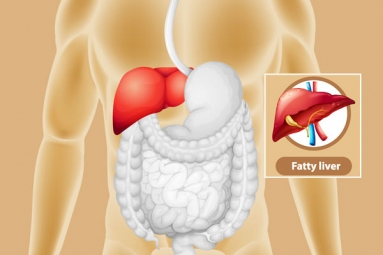

Liver issues, previously associated with older ages, are now becoming common in younger people too. A frequently encountered problem among today’s youth is non-alcoholic fatty liver disease (NAFLD). This condition is on the rise in young adults, largely due to unhealthy lifestyles, bad eating habits, overweight, and obesity. If not addressed promptly, a fatty liver can lead to serious health issues like non-alcoholic steatohepatitis (NASH), liver fibrosis, cirrhosis, or even liver cancer. There’s no need to panic just yet.